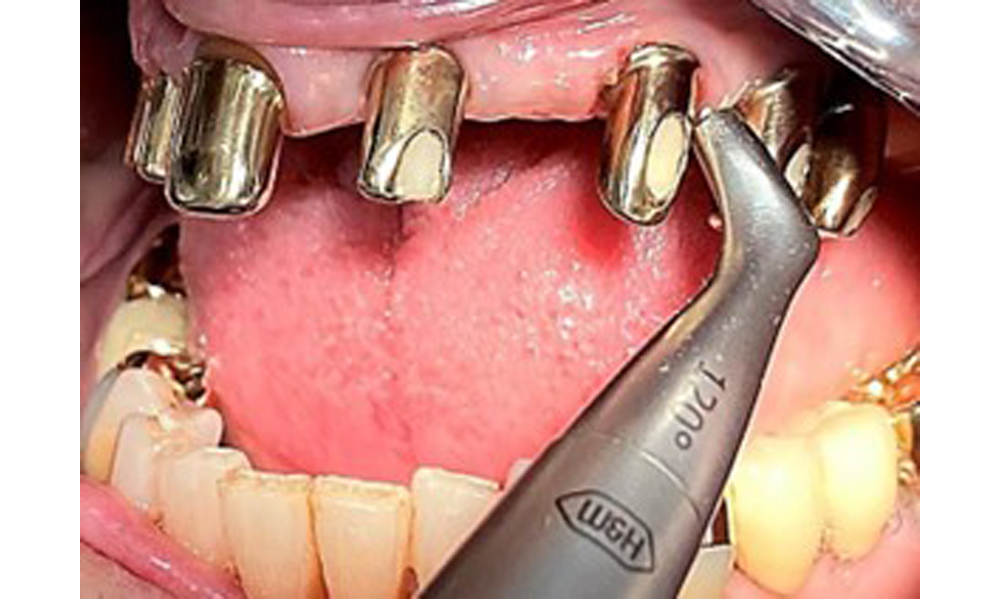

The patient was fitted with a combined removable maxillary telescopic prosthesis more than 25 years ago (Fig. 1, Fig. 2, Fig. 3) and is very happy with her dentures. The patient has an adequate fixed denture for the mandible (Fig. 4).

The dental findings are as follows: Combined removable implant and tooth-supported telescopic prostheses on implants 15, 13, 21, 23, 24, 25 and tooth 11 (Fig. 1, Fig. 2, Fig. 3). The patient was fitted with a fixed mandibular denture. Adequate bridges were present over 37 to 34 and 45 to 47 (Fig. 4), the crown margins were intact and there were no active caries. A composite filling with a marginal gap was present on tooth 43. There was mandibular gingival recession, exposing 1 to 3 mm of root surface. This also applies to 11.

Occlusal view: Maxilla with tooth and implant-supported telescopic prostheses.

Fig. 2: Occlusal view: Maxilla with tooth and implant-supported telescopic prostheses